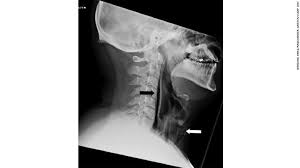

When you hold in a sneeze air and pressure can travel up your eustachian tubes small passageways linking your throat to your middle ear and cause your eardrum to rupture. But if you happen to be one of these unlucky cases wild said a holding in a sneeze may lead to several unhealthy situations. At worst you can rupture your eardrum or pop a blood vessel in your eye but that s unlikely. Some injuries from holding in a sneeze can be very serious such as ruptured brain aneurysms ruptured throat and collapsed lungs.